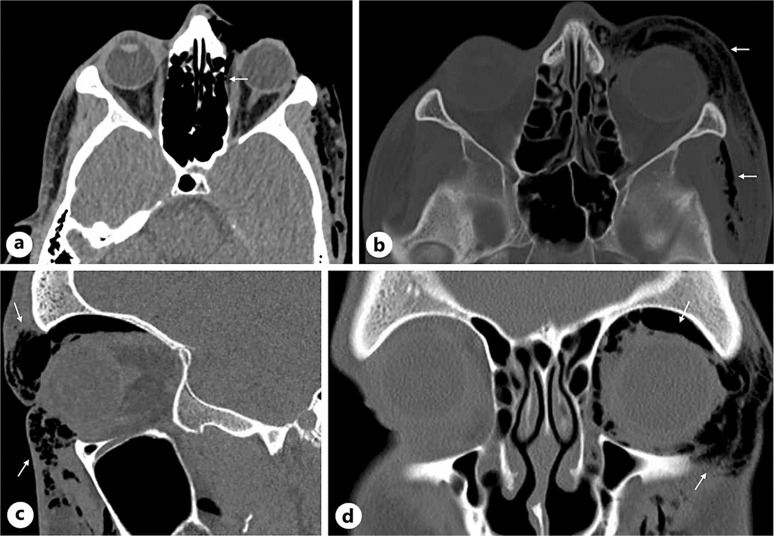

Case presentation: A 28-year-old man experienced a sudden onset of unilateral orbital and subcutaneous periorbital emphysema following Valsalva maneuver. He had unilateral subcutaneous emphysema, crepitus, violaceous discoloration of the lids, and chemosis of the palpebral conjunctiva. Visual acuity was intact, and intraocular pressure was mildly elevated. Imaging showed an idiopathic lamina papyracea dehiscence. The patient was advised of sinus precautions with uneventful spontaneous resolution and no visual sequelae.